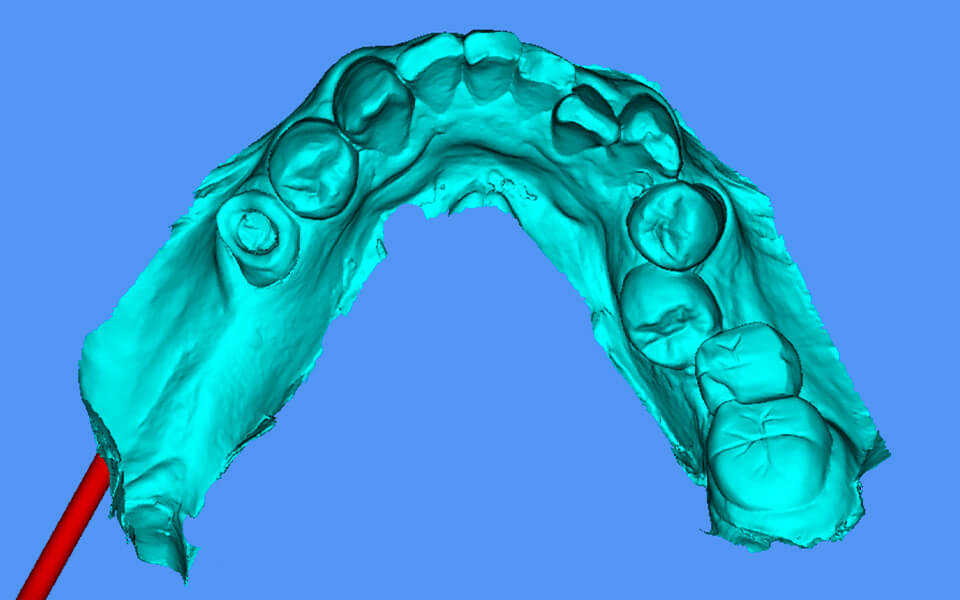

SMOP

スモップ

インプラント治療におけるコンピューターガイドシステムの一つで、CT診断によるシミュレーションを実際の口腔内で再現いたします。

これにより、より正確なインプラント埋入が可能になり、患者の負担を軽減する手術(フラップレス手術)も行える場合があります

特徴

• マッチング精度の徹底的追求

• 口腔内での適合度の追求

• さまざまな症例に対応

• 部分的骨支持にも対応可能

• インプラントシステムの多くに対応

• 複数のウィンドウ作製可能